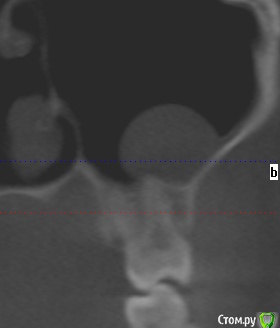

Добрый день коллеги,плановое удаление 8 зубов ,верхние в гайморовой ,что за образование в левой жалоб нет никаких.Что вы делаете при вскрытии пазухи?